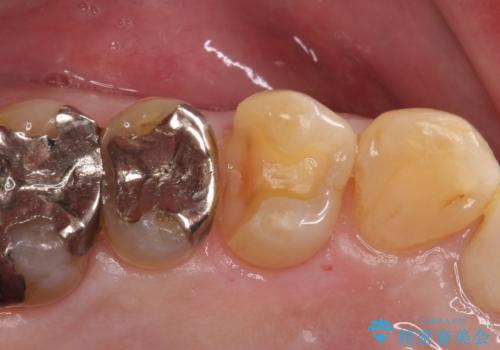

- 銀歯が取れたことを主訴に来院されました。

虫歯も認め、虫歯を除去したのちセラミックインレーにて修復しております。

適合のよい修復を行うことで、再び虫歯になることを予防します。